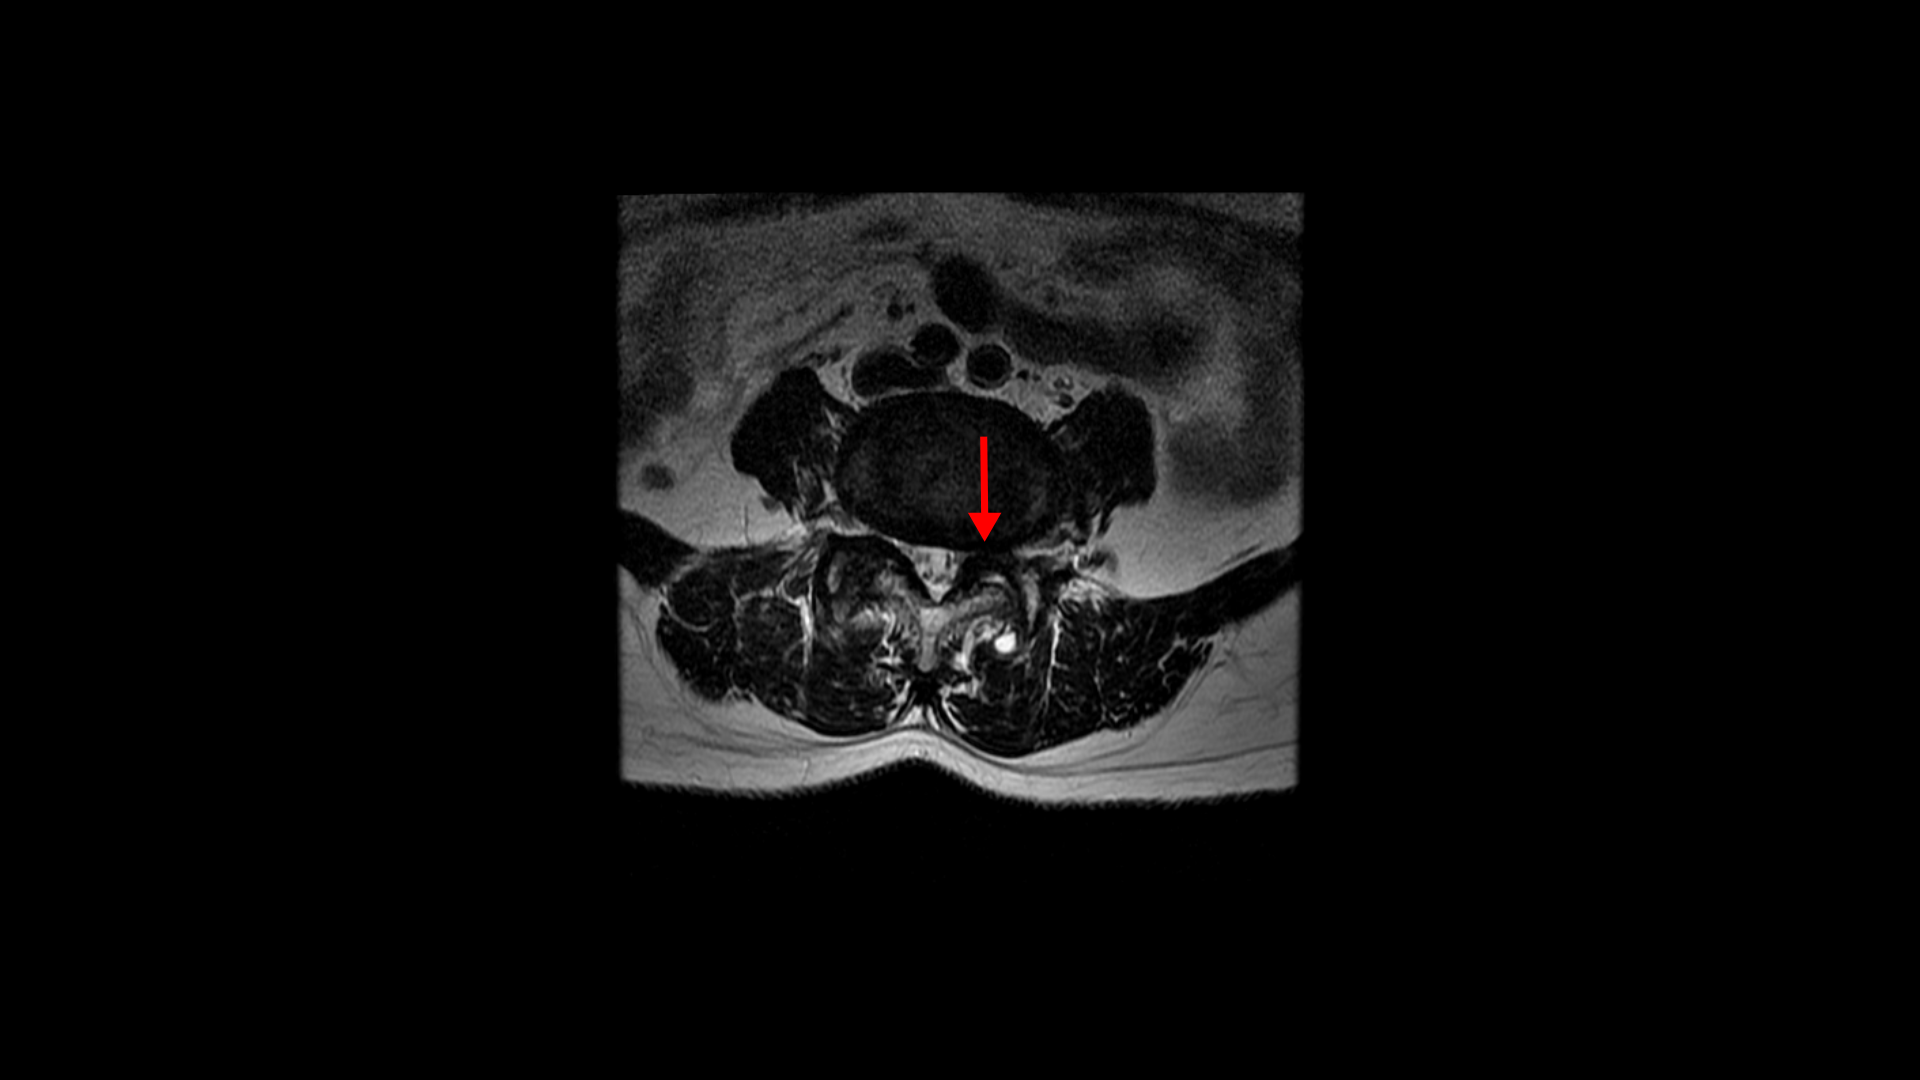

그런데 이 환자분의 제일 불편한 증상은 왼쪽이 아니고 오른쪽 엉치와 다리 증상입니다. 이분 오른쪽 신경 구멍들을 보면 전부 다 넓게 잘 열려 있습니다.

엉치와 다리 방사통을 일으킬만한 특별한 신경 눌림이 보이지 않는 것입니다. 그럼에도 불구하고 여러 마디의 전방전위증과 척추관 협착 그리고 디스크 탈출이 있으니까 그것을 원인으로 보고 신경 주사도 맞고 시술도 받으셨습니다. 그러나 별 효과는 없었습니다. 그리고 대학병원에서도 결국은 수술밖에 방법이 없다고 수술을 권유하였습니다.

이 환자분은 MRI에서 오른쪽에 신경 눌림이 심해 보이지 않는 상태에서 오른쪽에 심한 방사통과 함께 오른쪽 중둔근이 극심하게 뭉쳐있는 것이 확인되었습니다. 만일 이 근육들을 풀어서 하룻밤 사이에 방사통이 사라진다면 그건 명확히 근육성 방사통이었던 겁니다. 보통 단단하게 뭉쳐있는 근육에 의한 방사통이라해도 하루만에 치료가 되는 경우는 매우 드뭅니다. 특히 7년씩이나 방사통이 있었으면 근육이 뭉쳐도 정말 심하게 뭉쳐있을 거고 엉덩이 근육만이 아니라 허리 근육 및 다리 근육들도 다 뭉쳐있을 가능성이 높기 때문에 1-2주 정도 매일 4-5회 이상 다양한 방법으로 근육을 풀어주면서 쉬는 걸 반복하는, 즉 풀어주고 쉬고 풀어주고 쉬고 풀어주고 쉬고를 반복해야 극심하게 뭉친 근육이 풀립니다. 그래야 방사통이 사라지고 좋아지는 겁니다.